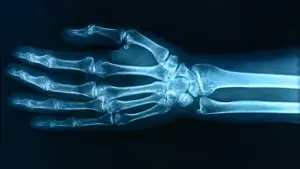

Поширені у воді та побутових речах PFAS (“вічні хімікати”) пов’язали зі зниженням щільності кісток у дітей. Найпомітніший сигнал — у 12-річних, де виявили зв’язок між однією з речовин і слабшими кістками передпліччя.

Найчіткіший зв’язок зафіксували для PFOA — ця речовина асоціювалася з нижчою щільністю кісток у 12 років. Для інших PFAS результати залежали від віку та часу впливу.

Зниження кісткової маси в дитинстві — не дрібниця. Це прямо пов’язано з ризиком переломів і навіть остеопорозу в майбутньому.

Дослідники оцінюють: різниця між високими й низькими рівнями PFAS може означати приблизно на 30% вищий ризик переломів — хоча це лише оцінка, а не доведений факт.